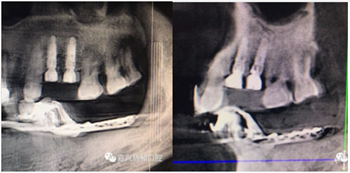

愈合基臺(tái)的置入及縫合

術(shù)后種植體位置與術(shù)前設(shè)計(jì)一致